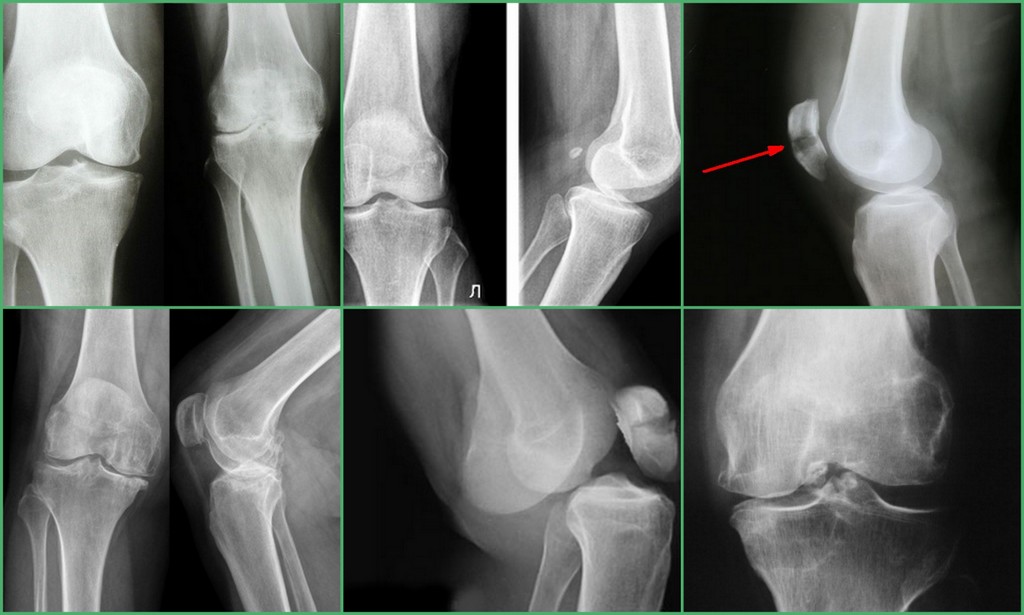

Медицинские снимки: рентген коленного сустава при остеопорозе